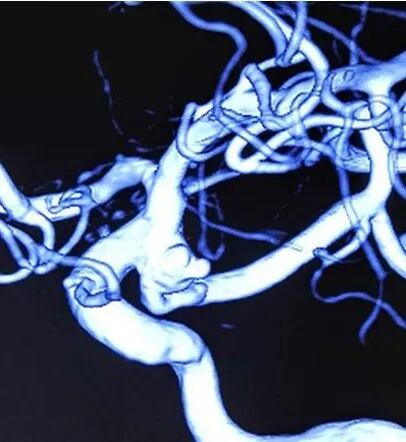

造影提示:左侧后交通动脉瘤。

压颈椎动脉造影提示:胚胎性大脑后动脉,且后交通动脉开口在动脉瘤体的中部。

家属拒绝开颅夹闭动脉瘤,介入治疗关键点是保护后交通,如果后交通开口靠近瘤颈,操作会简单一些,支架放颈内动脉辅助,栓塞动脉瘤时保留后交通开口即可,但这个后交通从瘤体中部发出,后交通必须支架保护了。颈内动脉也可置入支架。

这一类型动脉瘤颈内和后交通动脉内的两个支架如何选择是个问题。笔者经验后交通内支架以Enterprise或Neuroform首选,因为定位准确,支撑性好,而LVIS短缩影响定位和SAB楔形尾端干扰颈内动脉支架的原因为次选。

超选后交通动脉是关键,有时需要成袢技术,然而微导管的袢总是掉入瘤腔,术者希望导管袢跨过动脉瘤开口,如果能在动脉瘤口上架一桥,让袢过去就好了。

颈内动脉的另一根微导管就起到了“桥”的作用,袢轻松过动脉瘤开口,然后微导丝很容易进入后交通。

后交通动脉内均放了LVIS,通过测量准确定位,后交通内支架末端在动脉瘤开口。